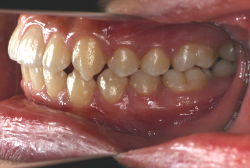

上顎前突

上顎前突(出っ歯)とは上顎が前に出ている状態です。この症状の特徴は、上下の歯並び全体の位置関係が相対的に上顎が優位になっていて、前歯が外に反っているだけでなく奥歯の位置関係も上が前にズレています。さらに凸凹の症状も合併していることがよくあり、上の前歯の見た目を気にして来院する方が多いのですが、実は今言った理由で噛み合わせにも異常があるため、このまま放置すると顎関節症という症状が出ることもあります。

「出っ歯を治したい」という主訴で来院したケースです。診断の結果、「2級1類の上顎前突+軽度叢生」と判明しました。2級というのは、基本的に出っ歯の噛み合わせになっていることを言います。その中でも上の前歯が著しく外に反っているケースを、「1類」といいます。初診時の横向きの写真を見ると、それがはっきり分かります。上の前歯に押されて唇も膨らんで、審美線をかなりオーバーしています(審美線とは、鼻の先端と顎の先端を結ぶ線のことで、この線よりも唇は内側にある方が良いとされています)。

このような症状の場合は、前歯を内側に入れるためにかなり大量の隙間を必要とします。通常は上下左右の小臼歯を抜歯させていただくのが正解です。治療後は歯の角度が正しくなっただけでなく、唇の審美性が大幅に改善しました。もちろん噛み合わせ的にも正しい状態が確立しています。